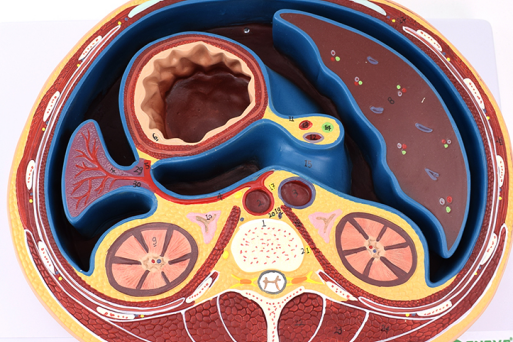

氩氦刀冷冻消融是通过将一根1.7-3毫米的中空钢针,穿刺进入病灶,先注入氩气,迅速降温至-160摄氏度左右,冰冻肿瘤数分钟,再注入氦气,快速升温至20-30摄氏度,让肿瘤细胞在短时间内冷冻及复温,对病灶组织进行物理性杀灭。